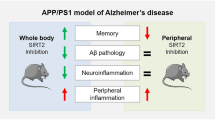

Yang W, Zou Y, Zhang M, Zhao N, Tian Q, Gu M, Liu W, Shi R et al (2015) Mitochondrial Sirt3 expression is decreased in APP/PS1 double transgenic mouse model of Alzheimer’s disease. Neurochem Res 40:1576–1582